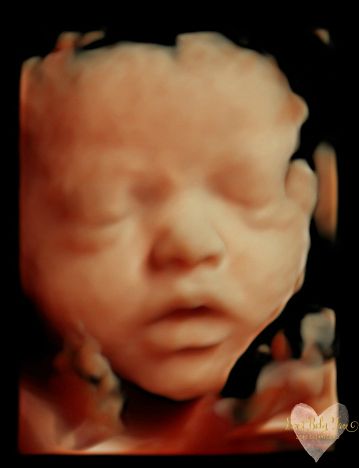

3D/4D/5D Ultrasound Gallery

Take a peek at our Photo Gallery. All of our 2D, 3D, 4D, HD elective ultrasound images are truly ours. They come directly off our machine from our highly trained staff. We can start getting great 3D/4D images as early as 10 weeks!